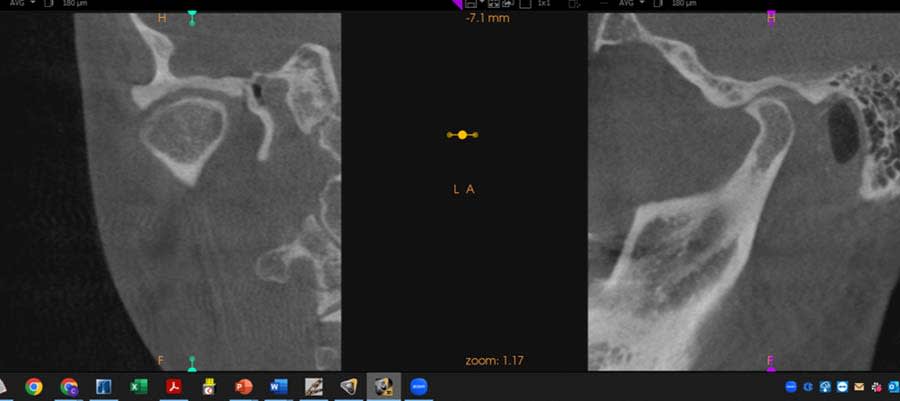

Functional: Moderate anterior attrition (1 mm to 1.5 mm) was noted, particularly on teeth Nos. 6 through 9 and 24 through 27, with no significant posterior wear or abfraction lesions. The patient reported slow progression of attrition on her front teeth that had stabilized over the past 5 years, corroborated by a historical photograph. Temporomandibular joint (TMJ) evaluation revealed a 40 mm maximum opening with slight right deviation, asymmetrical lateral movements (8 mm right and 11 mm left), and no pain or joint sounds. She had facial asymmetry as her chin point was 2 mm right of center. CBCT imaging showed a non-reducing anteriorly displaced disc in the right TMJ with osteophyte formation and reduced cortical bone, contrasting a normal left TMJ (Figure 6). Occlusal dysfunction was suspected due to her aberrant chewing pattern, which resulted in unilateral attrition and clenching. Her initial deprogramming identified the first contact on tooth No. 2 with a slide into maximum intercuspation, supporting an occlusal dysfunction diagnosis.